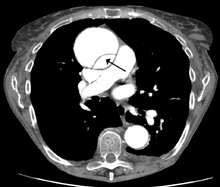

Computed tomography

CT with contrast demonstrating aneurysmal dilation and a dissection of the ascending aorta (type A Stanford)

Chest CT with descending (type B Stanford) aortic dissection (red circle)